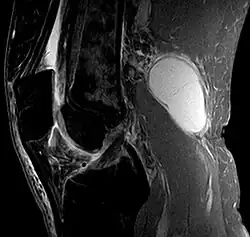

Diagnosis is by examination. A Baker's cyst is easier to see from behind with the patient standing with knees fully extended. It is most easily palpated (felt) with the knee partially flexed. Diagnosis is confirmed by ultrasonography, although if needed and there is no suspicion of a popliteal artery aneurysm then aspiration of synovial fluid from the cyst may be undertaken with care. An MRI image can reveal presence of a Baker's cyst.